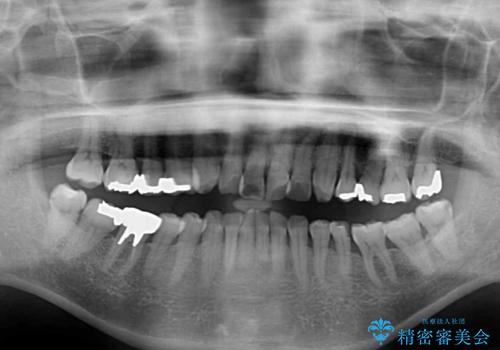

- 突出した口元を引っ込めることを希望して来院された患者様です。

上下左右第一小臼歯4本を抜歯して、口元を改善するワイヤー矯正を行うこととしました。